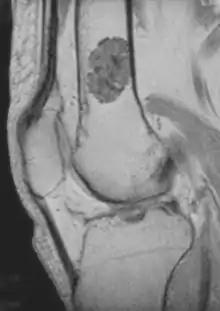

- magnetic resonance imaging (MRI)[7] - a diagnostic procedure that uses a combination of large magnets, radiofrequencies, and a computer to produce detailed images of organs and structures within the body. This test is done to rule out any associated abnormalities of the spinal cord and nerves.